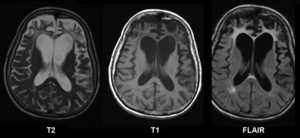

Brain MRI of a female of 65 years with frontotemporal dementia. Cortical and white matter atrophy of the frontal lobes is clear in all images.